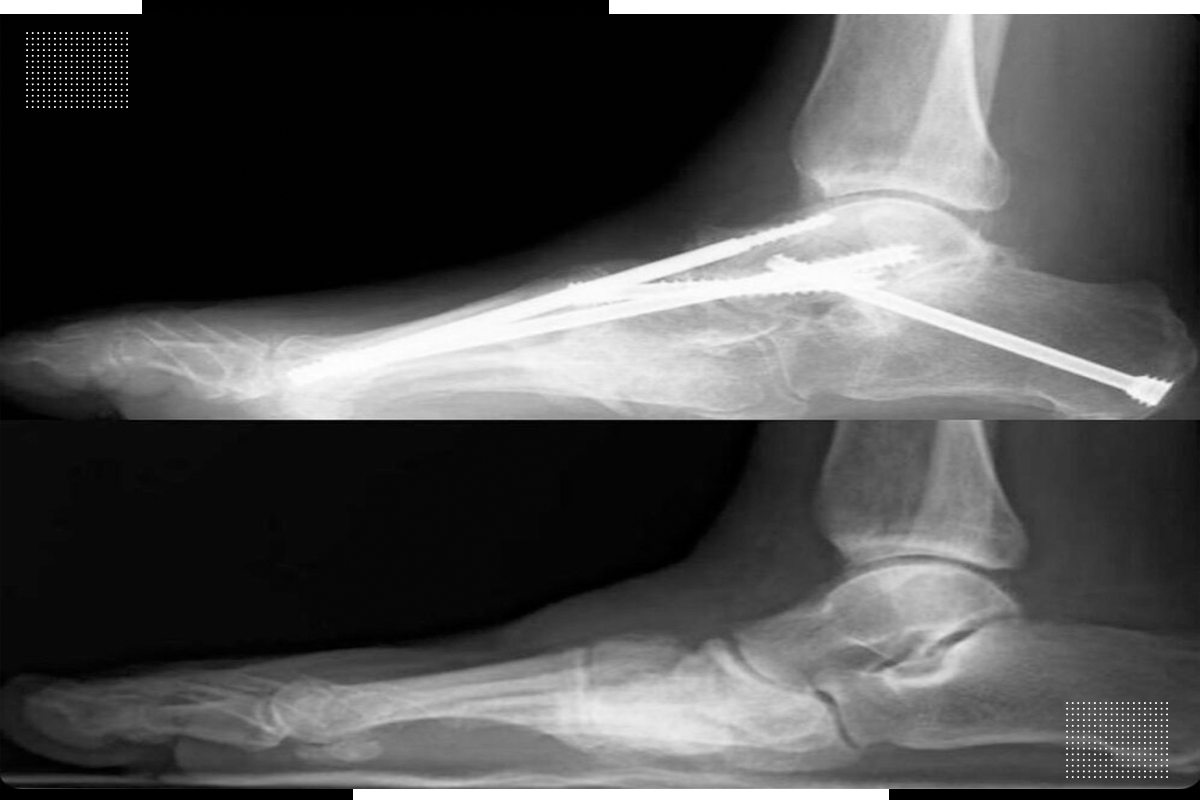

Ankle sprain is one of the most common injuries encountered during sports. Here are some statistics on the epidemiology of this pathology with different sports:

Pediatric injuries (or traumas) is prevailing day by day in young children. Because of their sundry nature in their origins, severity, and drastic effects on